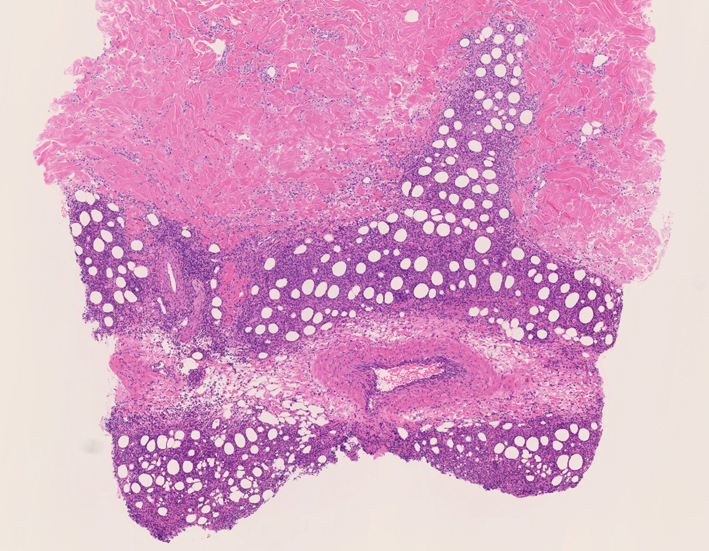

リンパ腫の定義: SPTCLは成熟細胞障害性T細胞(cytotoxic T-cell)由来で、皮下組織に脂肪識炎に似た組織像を呈しながら増殖する悪性リンパ腫。

皮膚生検組織 サムネイルをクリックすると大きな画像がみられます。

皮下組織に優位な, 小~中型 Tリンパ球の密な浸潤が特徴。ときに大型リンパ球や組織球が混在する。 リンパ球の異型は, わずかなものから明瞭な異型を示す症例までさまざまである。